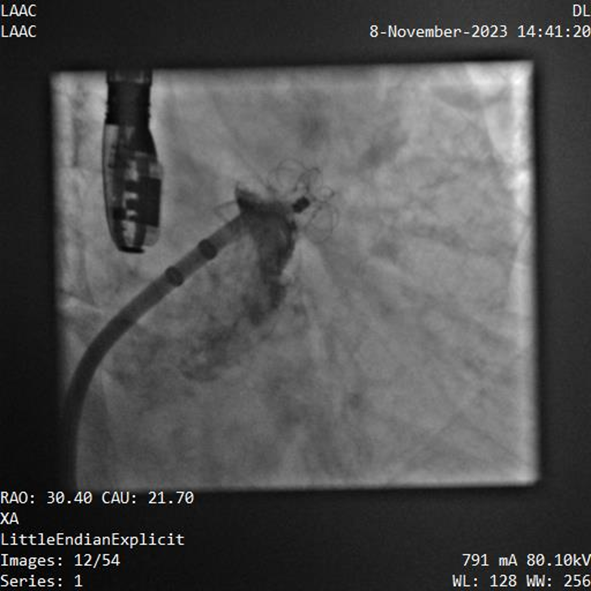

該例患者為男性58歲,陣發(fā)性房顫,9個(gè)月前突發(fā)急性腦梗死,3月前曾行房顫射頻消融術(shù)。2023年11月經(jīng)胸超聲心動(dòng)圖示左房內(nèi)徑46mm,經(jīng)食道超聲心動(dòng)圖示左心房及左心耳內(nèi)未見血栓形成,CHA2DS2-VASc評(píng)分3分,HAS-BLED評(píng)分2分。DSA測(cè)得左心耳開口直徑約23mm,錨定區(qū)域約18mm。

葛均波院士、周達(dá)新教授等經(jīng)詳細(xì)評(píng)估和討論后,認(rèn)為該受試者需要植入固定部20mm、封堵盤28mm的左心耳封堵器,為非常規(guī)固配規(guī)格,SimuLock的可選配組裝式設(shè)計(jì)精準(zhǔn)滿足患者需求。

手術(shù)過程順利,通過植入非常規(guī)固配規(guī)格的固定部20mm、封堵盤28mm的左心耳封堵器,實(shí)現(xiàn)左心耳完全封堵,達(dá)到手術(shù)預(yù)期效果,再次體現(xiàn)產(chǎn)品獨(dú)特的設(shè)計(jì)創(chuàng)新優(yōu)勢(shì)。

器械釋放后造影示封堵器展開良好,封堵完全